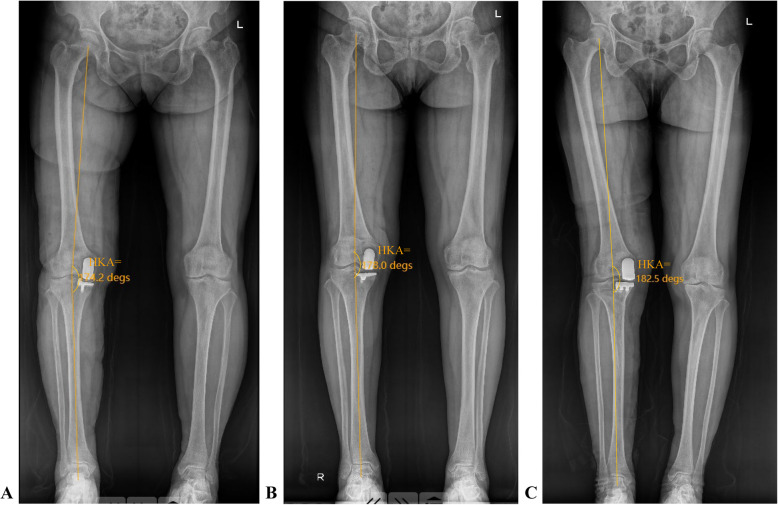

Methods: A retrospective analysis was conducted on individuals who received medial UKA at a specialized orthopedic hospital between January 1, 2024, and July 31, 2024. The aHKA was determined using the formula: medial proximal tibial angle (MPTA) minus lateral distal femoral angle (LDFA), plus 180°. The relationships between the postop HKA angle and the aHKA, MPTA, and LDFA were analyzed. Patients were further divided into three categories based on their postop HKA angle: greater than 180°, between 175° and 180°, and less than or equal to 175°. These groups were then compared in terms of aHKA, LDFA, MPTA, and preoperative HKA angle.

Results: A total of 242 patients (254 knees) were included in this study. The postop HKA was nearly equal to the preoperative aHKA (176.09° ± 2.86° vs. 176.23° ± 3.15°). Statistical analysis revealed a positive association between aHKA and postop HKA angle (R2 = 0.4595, P < 0.05), as well as between MPTA and postop HKA angle (R2 = 0.2072, P < 0.05). Conversely, a negative correlation was identified between LDFA and postop HKA angle (R2 = 0.2448, P < 0.05). These patterns held true for both fixed-bearing and mobile-bearing UKA prostheses. Notable differences among the three HKA groups were found regarding aHKA, MPTA, LDFA, and preoperative HKA angle (P < 0.05).